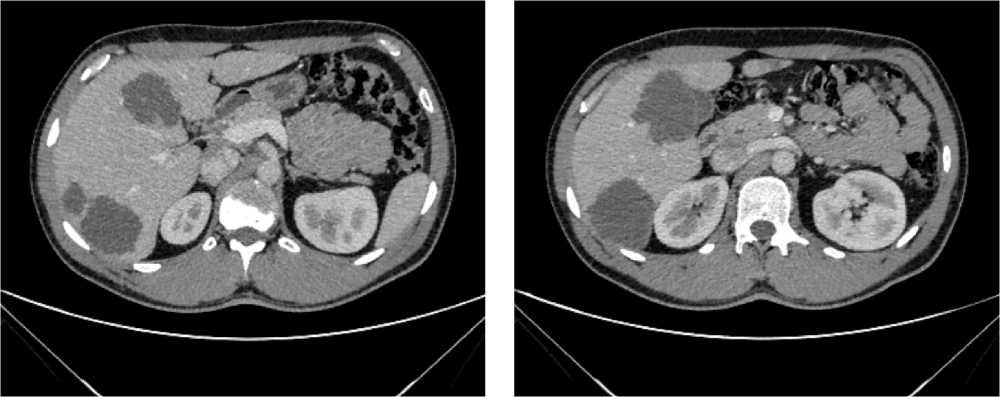

С июля 2022 г. у пациента отмечено появление эпизодов субфебрильной лихорадки. По результатам КТ органов брюшной полости от 08.2022 г. в проекции селезенки выявлена неоднородная инфильтрация с включениями, воздушной полостью в структуре, с тенденцией к отграничению и с распространением в параколическую клетчатку размерами 125 × 98 × 96 мм. Опухоль распространяется на большую кривизну желудка, вызывая утолщение стенки толщиной до 37 мм. По передней брюшной стенке справа отмечается округлое образование размерами 10 × 9 мм (рис. 5).

Рис. 5. Результаты компьютерной томографии органов брюшной полости у пациента 62 лет с диагнозом метастатический колоректальный рак с признаками микросателлитной нестабильности (август 2022 г., до лечения)

Fig. 5. Results of a CT scan of the abdomen of a 62-year-old patient with metastatic MSI-H colorectal cancer (August 2022, before treatment)

По результатам КТ органов брюшной полости (ОБП) от 08.2023, поддиафрагмально слева сохраняется инфильтрат 79 × 46 мм, распространяется на большую кривизну желудка, брюшину, диафрагму слева и по левому фланку брюшной полости. Желудок деформирован, стенки утолщены. Парагастральная и внутрибрюшинная клетчатка слева инфильтрирована. По брюшине сохраняются образования. Эффект лечения оценен как частичный регресс (рис. 6).

Рис. 6. Частичный регресс, по данным компьютерной томографии органов брюшной полости, на фоне иммунотерапии пембролизумабом у пациента 63 лет с диагнозом метастатический колоректальный рак с признаками микросателлитной нестабильности (август 2023 г.)

Fig. 6. Partial regression according to abdominal CT scan during immunotherapy with pembrolizumab in a 63-year-old patient with metastatic MSI-H colorectal cancer (August 2023)